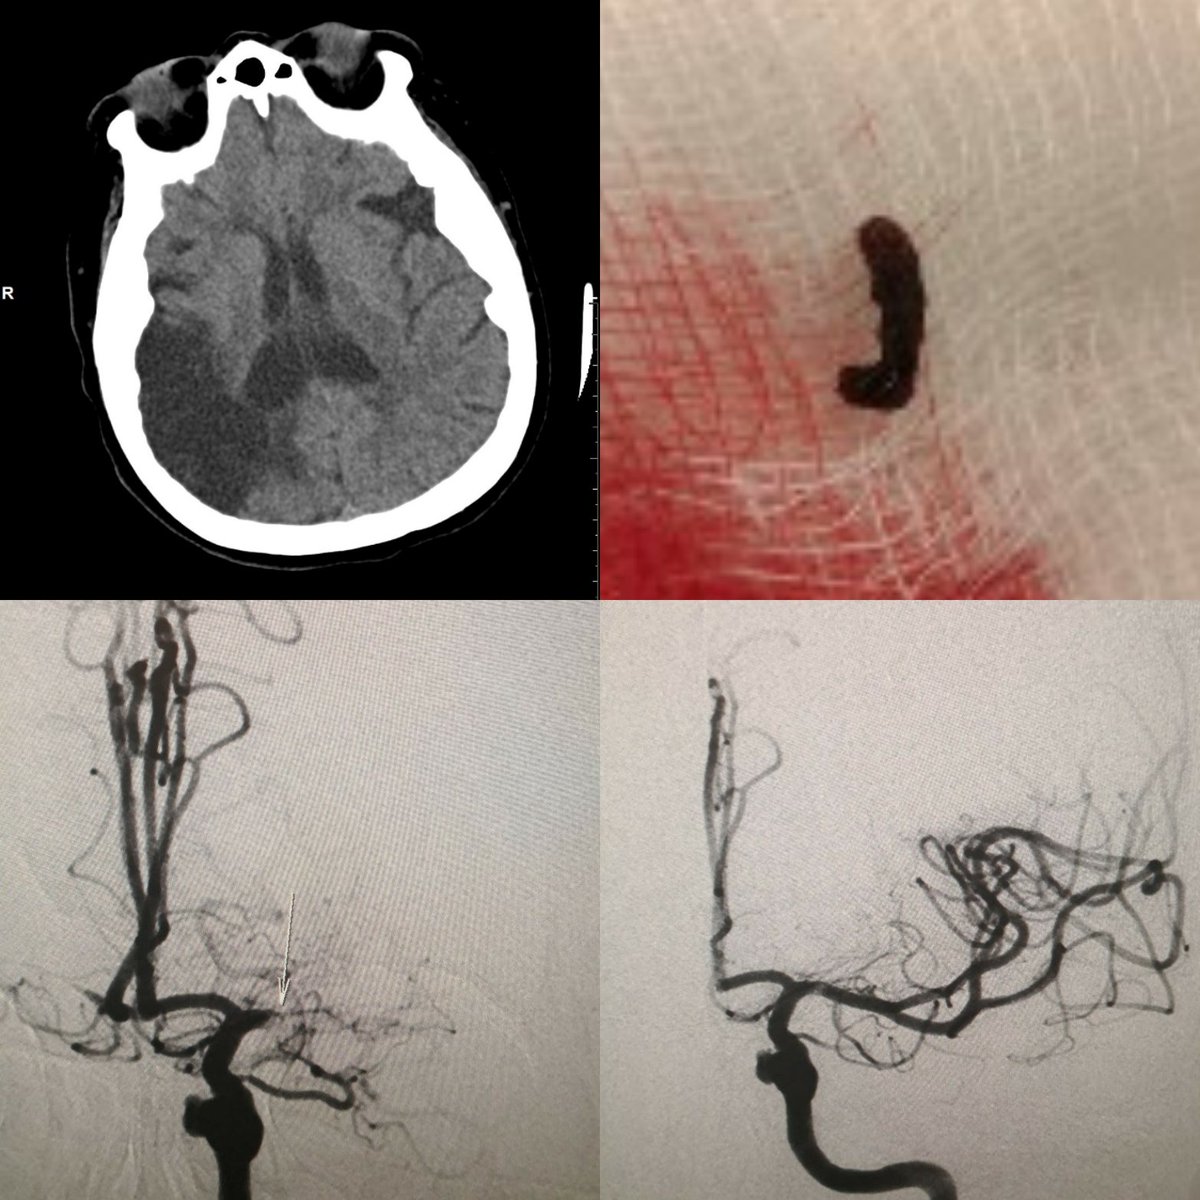

Behind every stroke is a story. She is mRS 5 at baseline (left hemiplegia), but who are we to judge others' quality of life? She could talk, smile and kiss her husband, how do you not treat her? Who cares about your "mRS 0-2" statistics, it's all about the patient. Always

SuspectedLVO's tweet image. Behind every stroke is a story. She is mRS 5 at baseline (left hemiplegia), but who are we to judge others' quality of life? She could talk, smile and kiss her husband, how do you not treat her? Who cares about your "mRS 0-2" statistics, it's all about the patient. Always